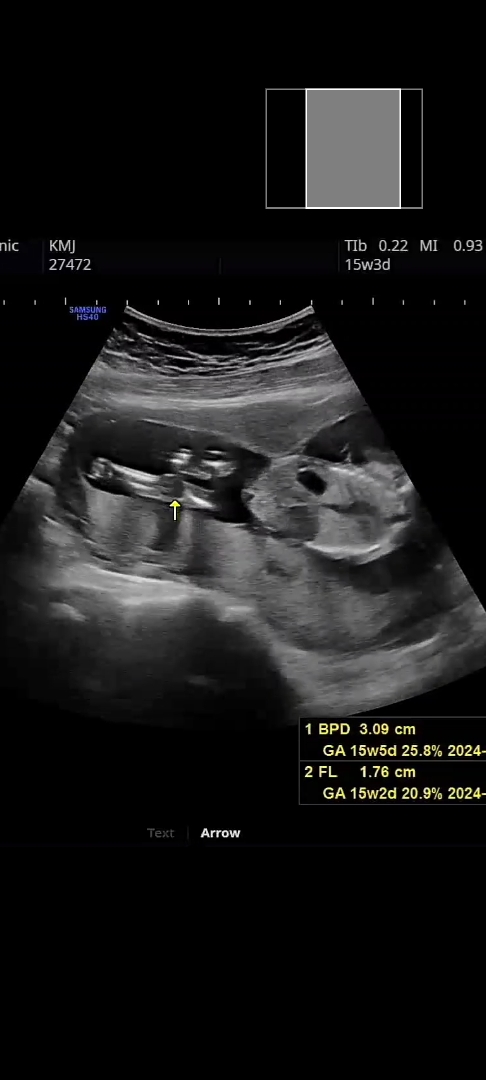

혹시 성별보이실까요?